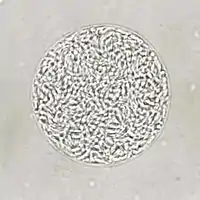

T. gondii oocysts in a fecal flotation